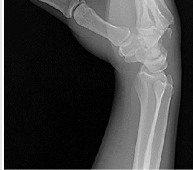

Question 8:

Which phase of fracture healing is most dependent on the inflammatory cascade initiated by macrophages and platelets?

Correct Answer: Hematoma formation and inflammation

Explanation:

The initial phase of fracture healing is the hematoma formation and inflammatory phase. Platelets and macrophages release cytokines (e.g., PDGF, TGF-beta) that recruit mesenchymal stem cells and initiate the healing process.